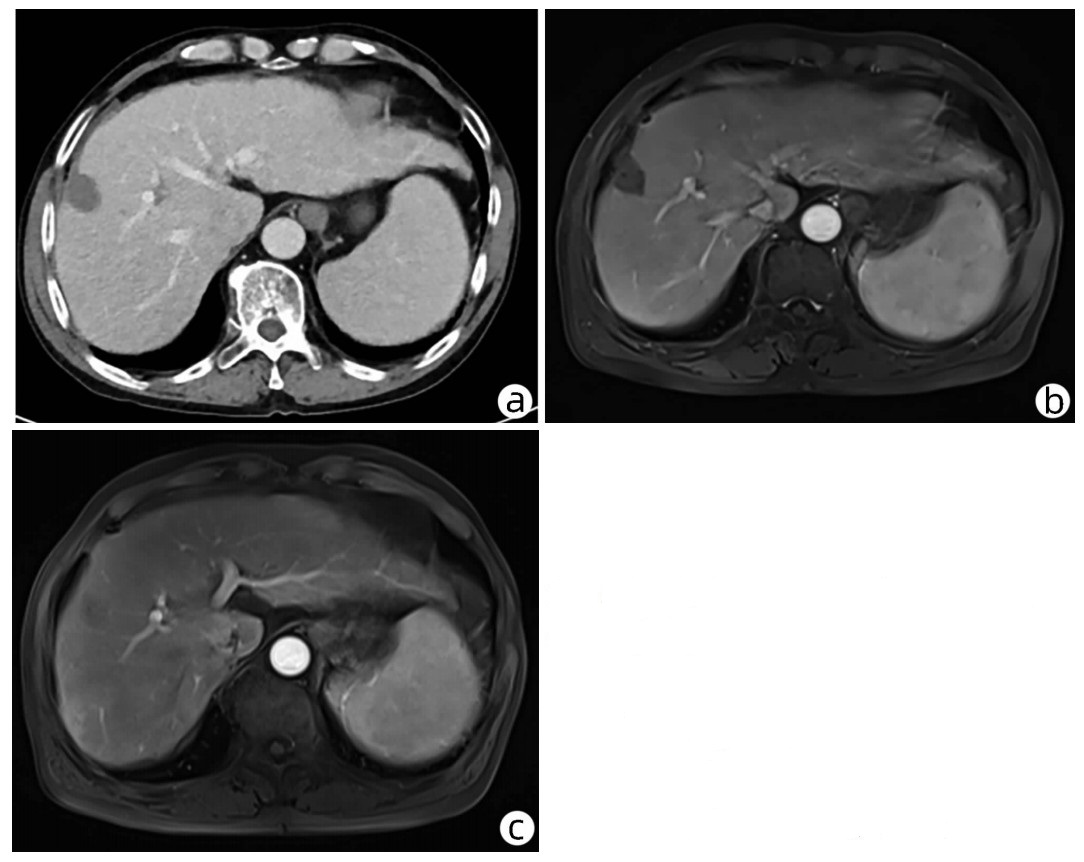

10例儿童肝糖原累积病临床及病理学分析

赵素贤, 刘世恒, 李文聪, 韩芳, 刘树红, 张庆山, 任伟光, 孔令波, 付娜, 王荣琦, 孔丽, 南月敏, 赵景民

2022, 38(8): 1839-1842. DOI: 10.3969/j.issn.1001-5256.2022.08.022

摘要(1407) HTML (512) PDF (2394KB)(109)

摘要:

目的  探讨儿童糖原累积病(GSD)的临床及病理学特点。  方法  选择2002年1月—2022年1月河北医科大学第三医院及解放军第五医学中心经病史、肝脏生化及肝活组织检查确诊的GSD 10例,对比分析人群特征、临床表现、生化指标、肝组织病理学特点。  结果  10例患儿发育迟缓,矮小,均表现为肝功能异常,轻度乏力、纳差、尿黄、眼黄,4例患者肝脾肿大。6例患者有低血糖的临床表现;1例患儿双侧腓肠肌肥大,Gower征阳性。2例患儿巨细胞病毒IgG阳性。肝组织病理学表现肝细胞弥漫性肿大,胞浆空淡,核小居中似植物细胞状,伴或不伴纤维组织增生。  结论  GSD患者多数有发育迟缓、转氨酶异常,肝组织病理检查有其特异性病理特征。